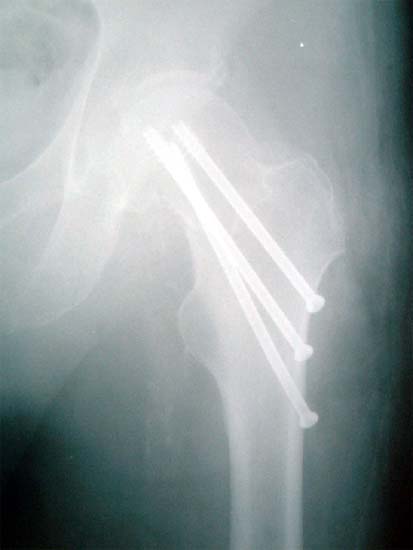

股骨颈骨折,采用闭合空心钉内固定。